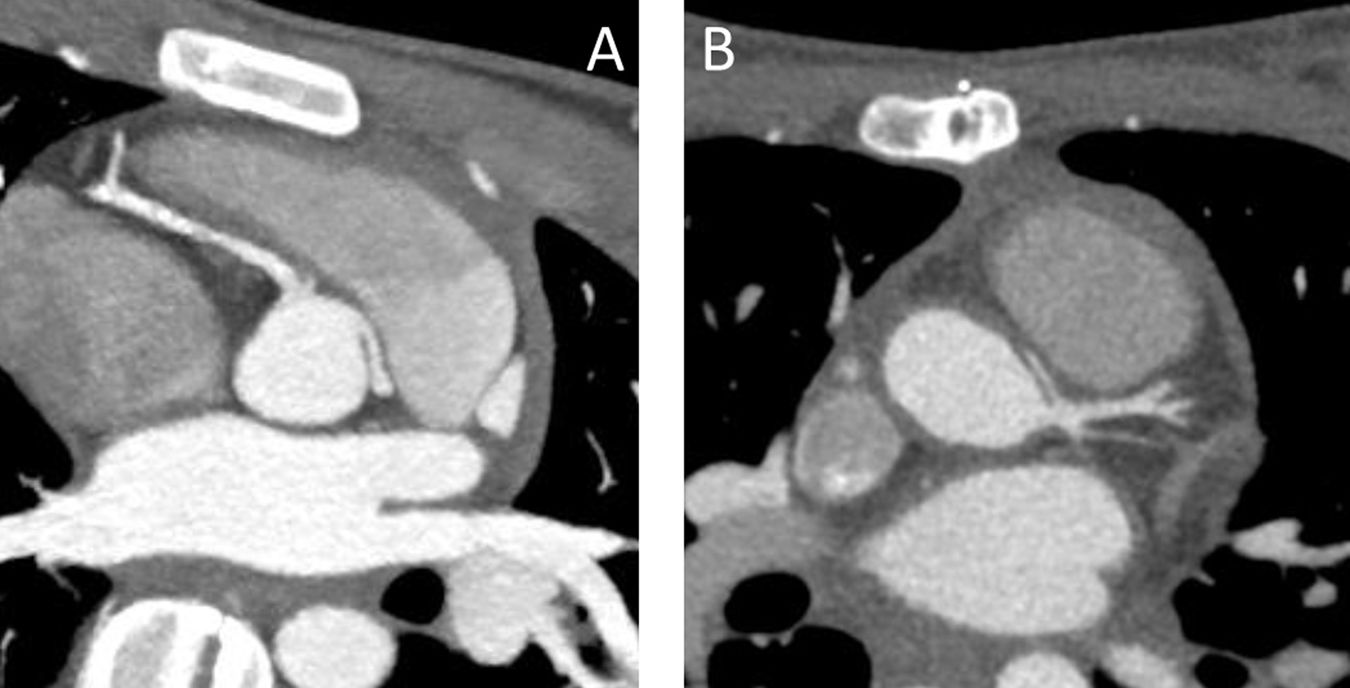

Salvo un caso, todos comenzaron con síncope o angina, y 6 de ellos (adolescentes n.° 2, 4, 5, 7, 9 y 10) durante la práctica deportiva. El restante fue detectado en una valvuloplastia aórtica quirúrgica (menor de un año, n.° 11). En el paciente n.° 13, diagnosticado de estenosis aórtica, se encontró la anomalía coronaria durante un cateterismo preoperatorio. Los estudios se completaron mediante ecografía, prueba de esfuerzo (positiva en todos) y tomografía axial computarizada (TAC) (fig. 1A). En un caso (n.° 4) la coronaria era única. El paciente n.° 6 presentaba antecedentes familiares de la misma enfermedad (padre con CD de origen anómalo en seno izquierdo, operado de revascularización coronaria).

Nuestro protocolo de seguimiento, basado en las guías descritas7,8, incluye prueba de esfuerzo precoz antes de permitir retomar actividades deportivas y la TAC durante el primer año, además de sucesivas TAC cada 5 años. El seguimiento ha sido completo con un rango de 3 meses a 7 años. Las imágenes de la TAC del postoperatorio (fig. 1B) muestran patrón coronario permeable en todos los casos.